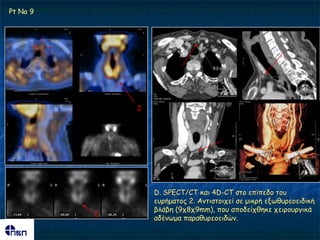

C. SPECT/CT θαη 4D-CT ζημ επίπεδμ ημο εονήμαημξ 1.

Πνόθεηηαη γηα μπίζζηα επέθηαζε ημο ΔΓ ιμβμύ ημο

ζονεμεηδμύξ (με μηθνμ-μδώδε οθή), πμο πηζακόηενα

δηθαημιμγεί ηεκ πνόζιερε ημο ηεπκεηίμο

Pt No 9

D. SPECT/CT θαη 4D-CT ζημ επίπεδμ ημο

εονήμαημξ 2. Ακηηζημηπεί ζε μηθνή ελςζονεμεηδηθή

βιάβε (9π8π9mm), πμο απμδείπζεθε πεηνμονγηθά

2

αδέκςμα παναζονεμεηδώκ.